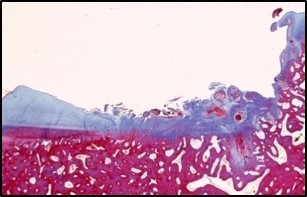

What does this show?

Osteochondrosis

Cartilage necrosis forms the OCD. Result of necrotic cartilage blood canals